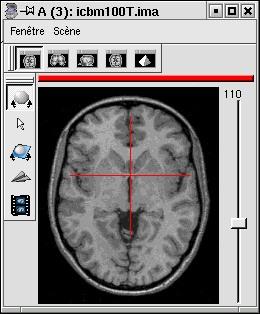

- MNI from Mritotal: resolution 1x1x1mm

![]()